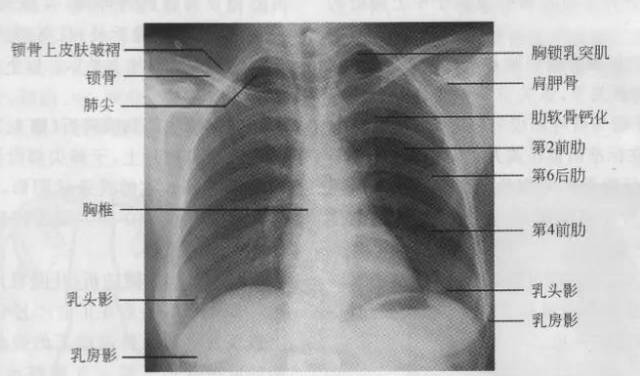

7.胸廓

正常胸廓由软组织与骨骼组成,两侧对称。

①骨性结构: 肋骨、锁骨、肩胛骨、胸椎

②软组织结构:胸锁乳头肌、锁骨上皮肤皱褶、胸大肌、女性乳房 / 乳头